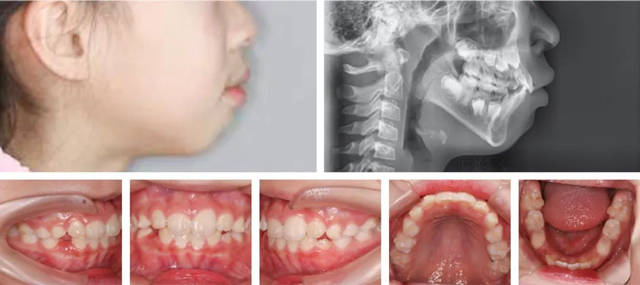

矫正半年后

经过半年的矫正,家长对朵朵牙齿的整齐效果非常满意。孙叡医生强调,早期矫正并不是简单的纠正牙齿问题,而是引导颌骨正常生长发育,因此建议更多家长能像朵朵妈妈一样,多关注孩子牙齿萌出、生长以及颌面发育的情况,如发现问题可及时到专业口腔机构就诊。